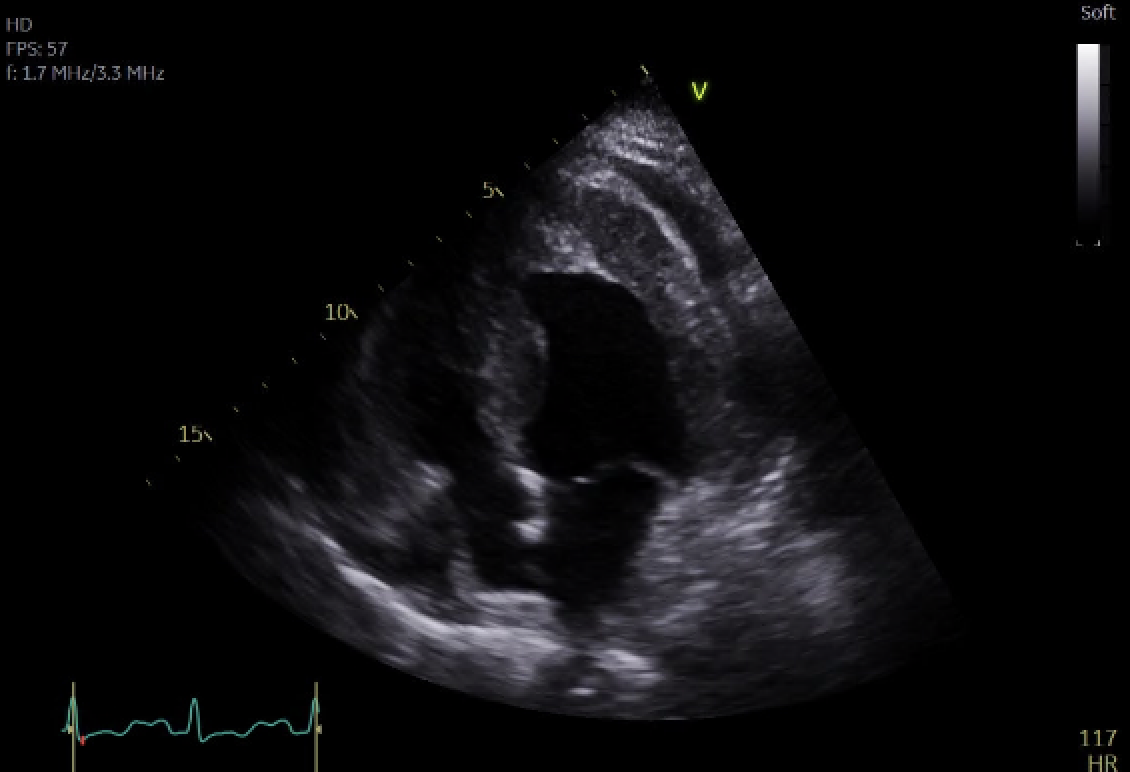

Figure 3; Comparison Of Initial And Follow Up CMR Studies Illustrating Initial Infiltration Followed By Widespread Oedema and Thrombus Formation